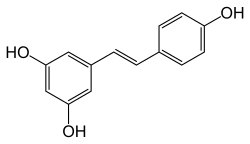

Studies in rats and mice have found that natural phenols such as resveratrol and curcumin can prevent the negative effects of the AGEs.[46][47]